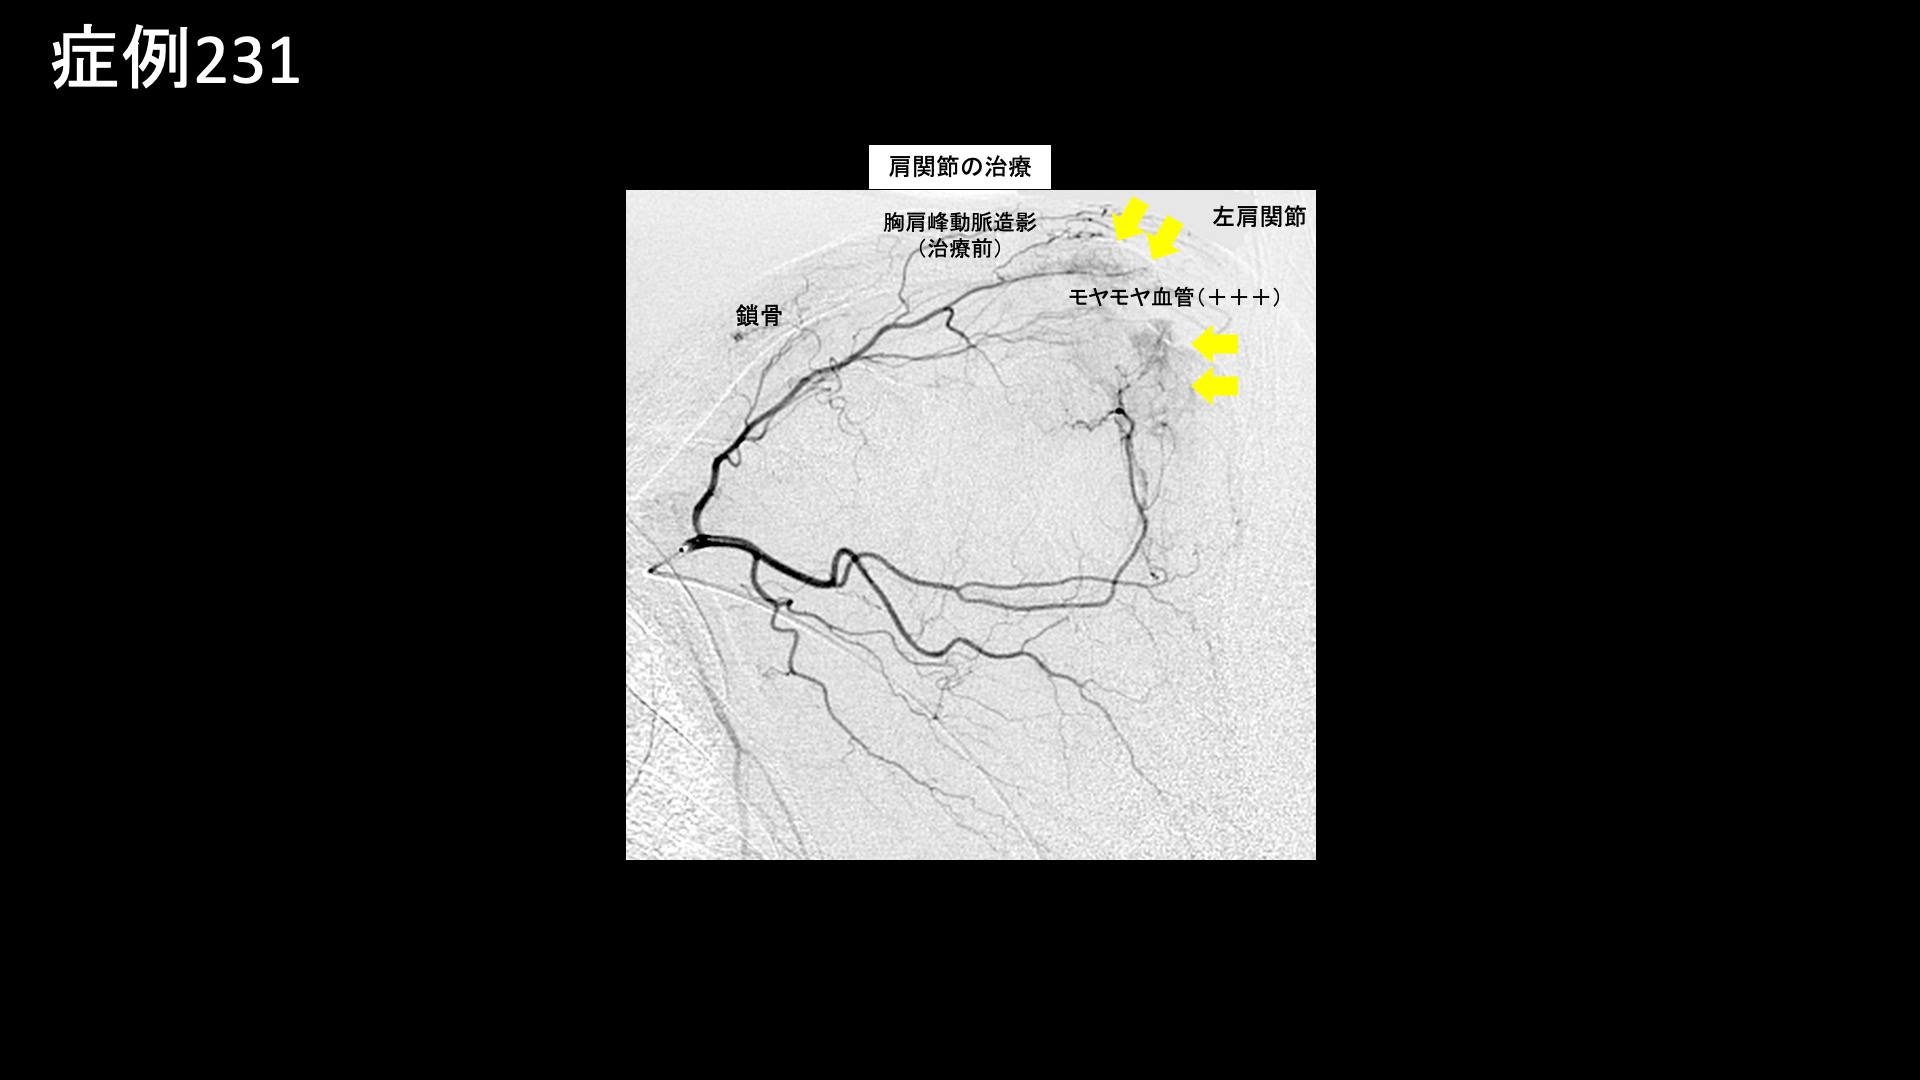

肩:肩こり・四十肩・五十肩 【50代:男性】肩腱板断裂手術後の遺残痛、及び再断裂による痛みに対するモヤモヤ血管治療(腱板断裂、手術後遺症、再断裂、肩関節周囲炎) 2025.08.26 鴨井院長による動画解説 受診までの経過 荷物運搬などの重労働により1年半前から左肩が痛むようになり、MRI検査で腱板断裂と診断されました。腕が全く上がらなくなってしまい、10ヶ月前に手術を受けました。入院は1ヶ月に及びましたが、腕が挙がるようになりました。しかし、痛みがとれず、じっとしていればよいものの、動かすと痛みが生じていました。MRI検査では、手術で縫合した部分の一部に再断裂を指摘されていました。リハビリを続けていましたが、リハビリで痛みを良くすることはできないと言われ、当院を受診されました。 診察時の所見 肩関節の可動域をチェックすると、外転、屈曲で軽度の制限がありましたが、日常生活には支障をきたさないくらいに保たれていました。レントゲンでは特に異常はありませんでした。エコー検査をすると、肩関節の前方において、腱板疎部や上腕二頭筋長頭腱周囲にモヤモヤ血管を反映した異常血流信号を認めたほか、上方腱板に断裂所見を認めました。腱板断裂後、手術により可動域は改善したものの、一定の痛みが残存し、さらに再断裂に伴う炎症も相加されている状態でした。治療適応と判断し、モヤモヤ血管(病的新生血管)に対する運動器カテーテル治療(微細動脈塞栓術)を受けていただきました。 治療の所見 血管造影を行うと、胸肩峰動脈でモヤモヤ血管が濃染像として描出されました。治療後は画像上速やかに消失しました。その他複数個所の治療を行い終了しました。 治療後の経過 治療後1週間で、左上腕の痛みが消失しました。肩関節前方の痛みはまだ残っていましたが、それも1ヶ月経過するうちに無くなりました。治療後2ヶ月、元々の痛みは取れた感じがする一方で、痛くなかった部位が少し痛み、特に腕を前方に伸ばしたときに痛みがありました。術前に比べればかなり楽になっており、日常生活での支障はないとのことでした。治療後3ヶ月、痛みはほぼ消失しました。前述の痛みがまだ多少残っているものの、自然軽快が見込まれたため、終診としました。腱板断裂による痛みについては、8-9割の痛みが取れて日常生活に支障をきたさなくなった後も、完全に消失するには半年~1年かかることもあります。その内に気にならなくなり、いつの間にか治っているという感覚になる方もおられます。 本症例では、肩関節への過負荷が原因でした。手術後の再断裂リスクは新規の断裂よりも高いのですが、お仕事柄、今後も過負荷による再断裂が懸念されます。無理を重ねないよう、慎重にお過ごしいただきたいと思います。 腱板疾患の詳しい病状説明はこちら 【60代:男性】ゴルフのフルスイングで生じる腰痛。仙腸関節障害に対するカテーテル治療(仙腸関節障害、筋・筋膜性疼痛症候群) 前の記事 【50代:男性】新型コロナウイルスワクチン接種後、鬼の手に⁉ 誰にも理解してもらえず3年間苦しんだ両肩~両手指の痛み(新型コロナウイルスワクチン接種後遺症、副反応、SIRVA、肩関節周囲炎、手指変形性関節症) 次の記事